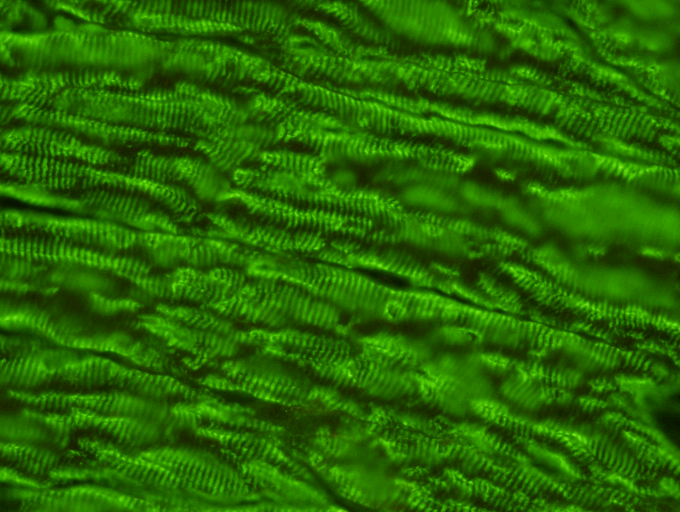

Striated Muscle Antibody Test Kit  Indirect Immunofluoresence assay  for the detection of Striated antibodies in human serum on primate or rat striated muscle sections. Clinical and experimental evidence strongly suggests that circulating antib

Striated Muscle Antibody Test Kit

Indirect Immunofluoresence assay  for the detection of Striated antibodies in human serum on primate or rat striated muscle sections. Clinical and experimental evidence strongly suggests that circulating antibodies directed against acetylcholine receptor (AChR) and muscle cell antigens are more important in the pathogenesis of myasthenia gravis.

5848L/5848RL  48 Test Kit

5896L/5896RL  96 Test Kit